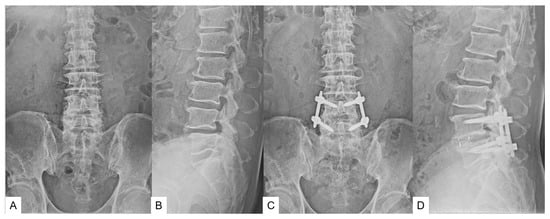

The patient underwent L4-5 OLIF because of low back pain and left sciatica (Figure 5).

Figure 5. 75-year-old man, L4 degenerative spondylolisthesis, L4/5 oblique lumbar interbody fusion. (A): Preoperative anteroposterior radiogram, (B): Preoperative lateral radiogram (L4–5 local lordosis 8 degrees), (C): Postoperative anteroposterior radiogram, (D): Postoperative anteroposterior radiogram (L4–5 local lordosis 19 degrees).